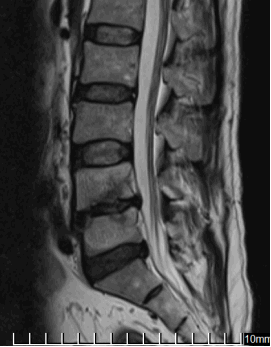

На МРТ в телах VL4-5 сигнал неоднородно снижен. Межтеловая щель сужена. Суставные поверхности неровные с узурацией, с краевыми остеофитами. Мягкие ткани вокруг инфильтрированы, утолщены, абсцессов нет. Спинномозговой канал сужен. За счет протрузии дисков VL4-5, VL5-S1 позвонков. Повышенный сигнал от тел остальных поясничных позвонков.

Рис. 1. МРТ до операции лазерной вапоризации межпозвонкового диска VL4-5

Рис. 2. МРТ при поступлении